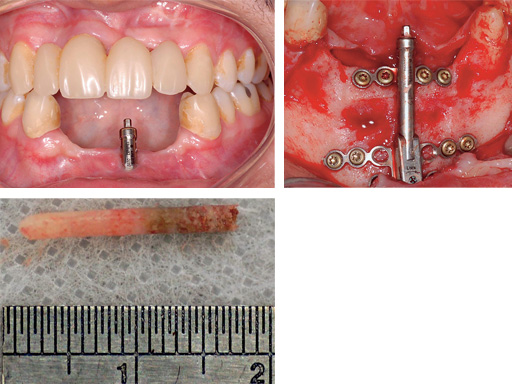

Maxillary distraction in a 34-year-old male after periodontal disease.

Mandibular distraction in a 20-year-old male after trauma. The bone biopsy shows a darker shading where the bone is newly formed.